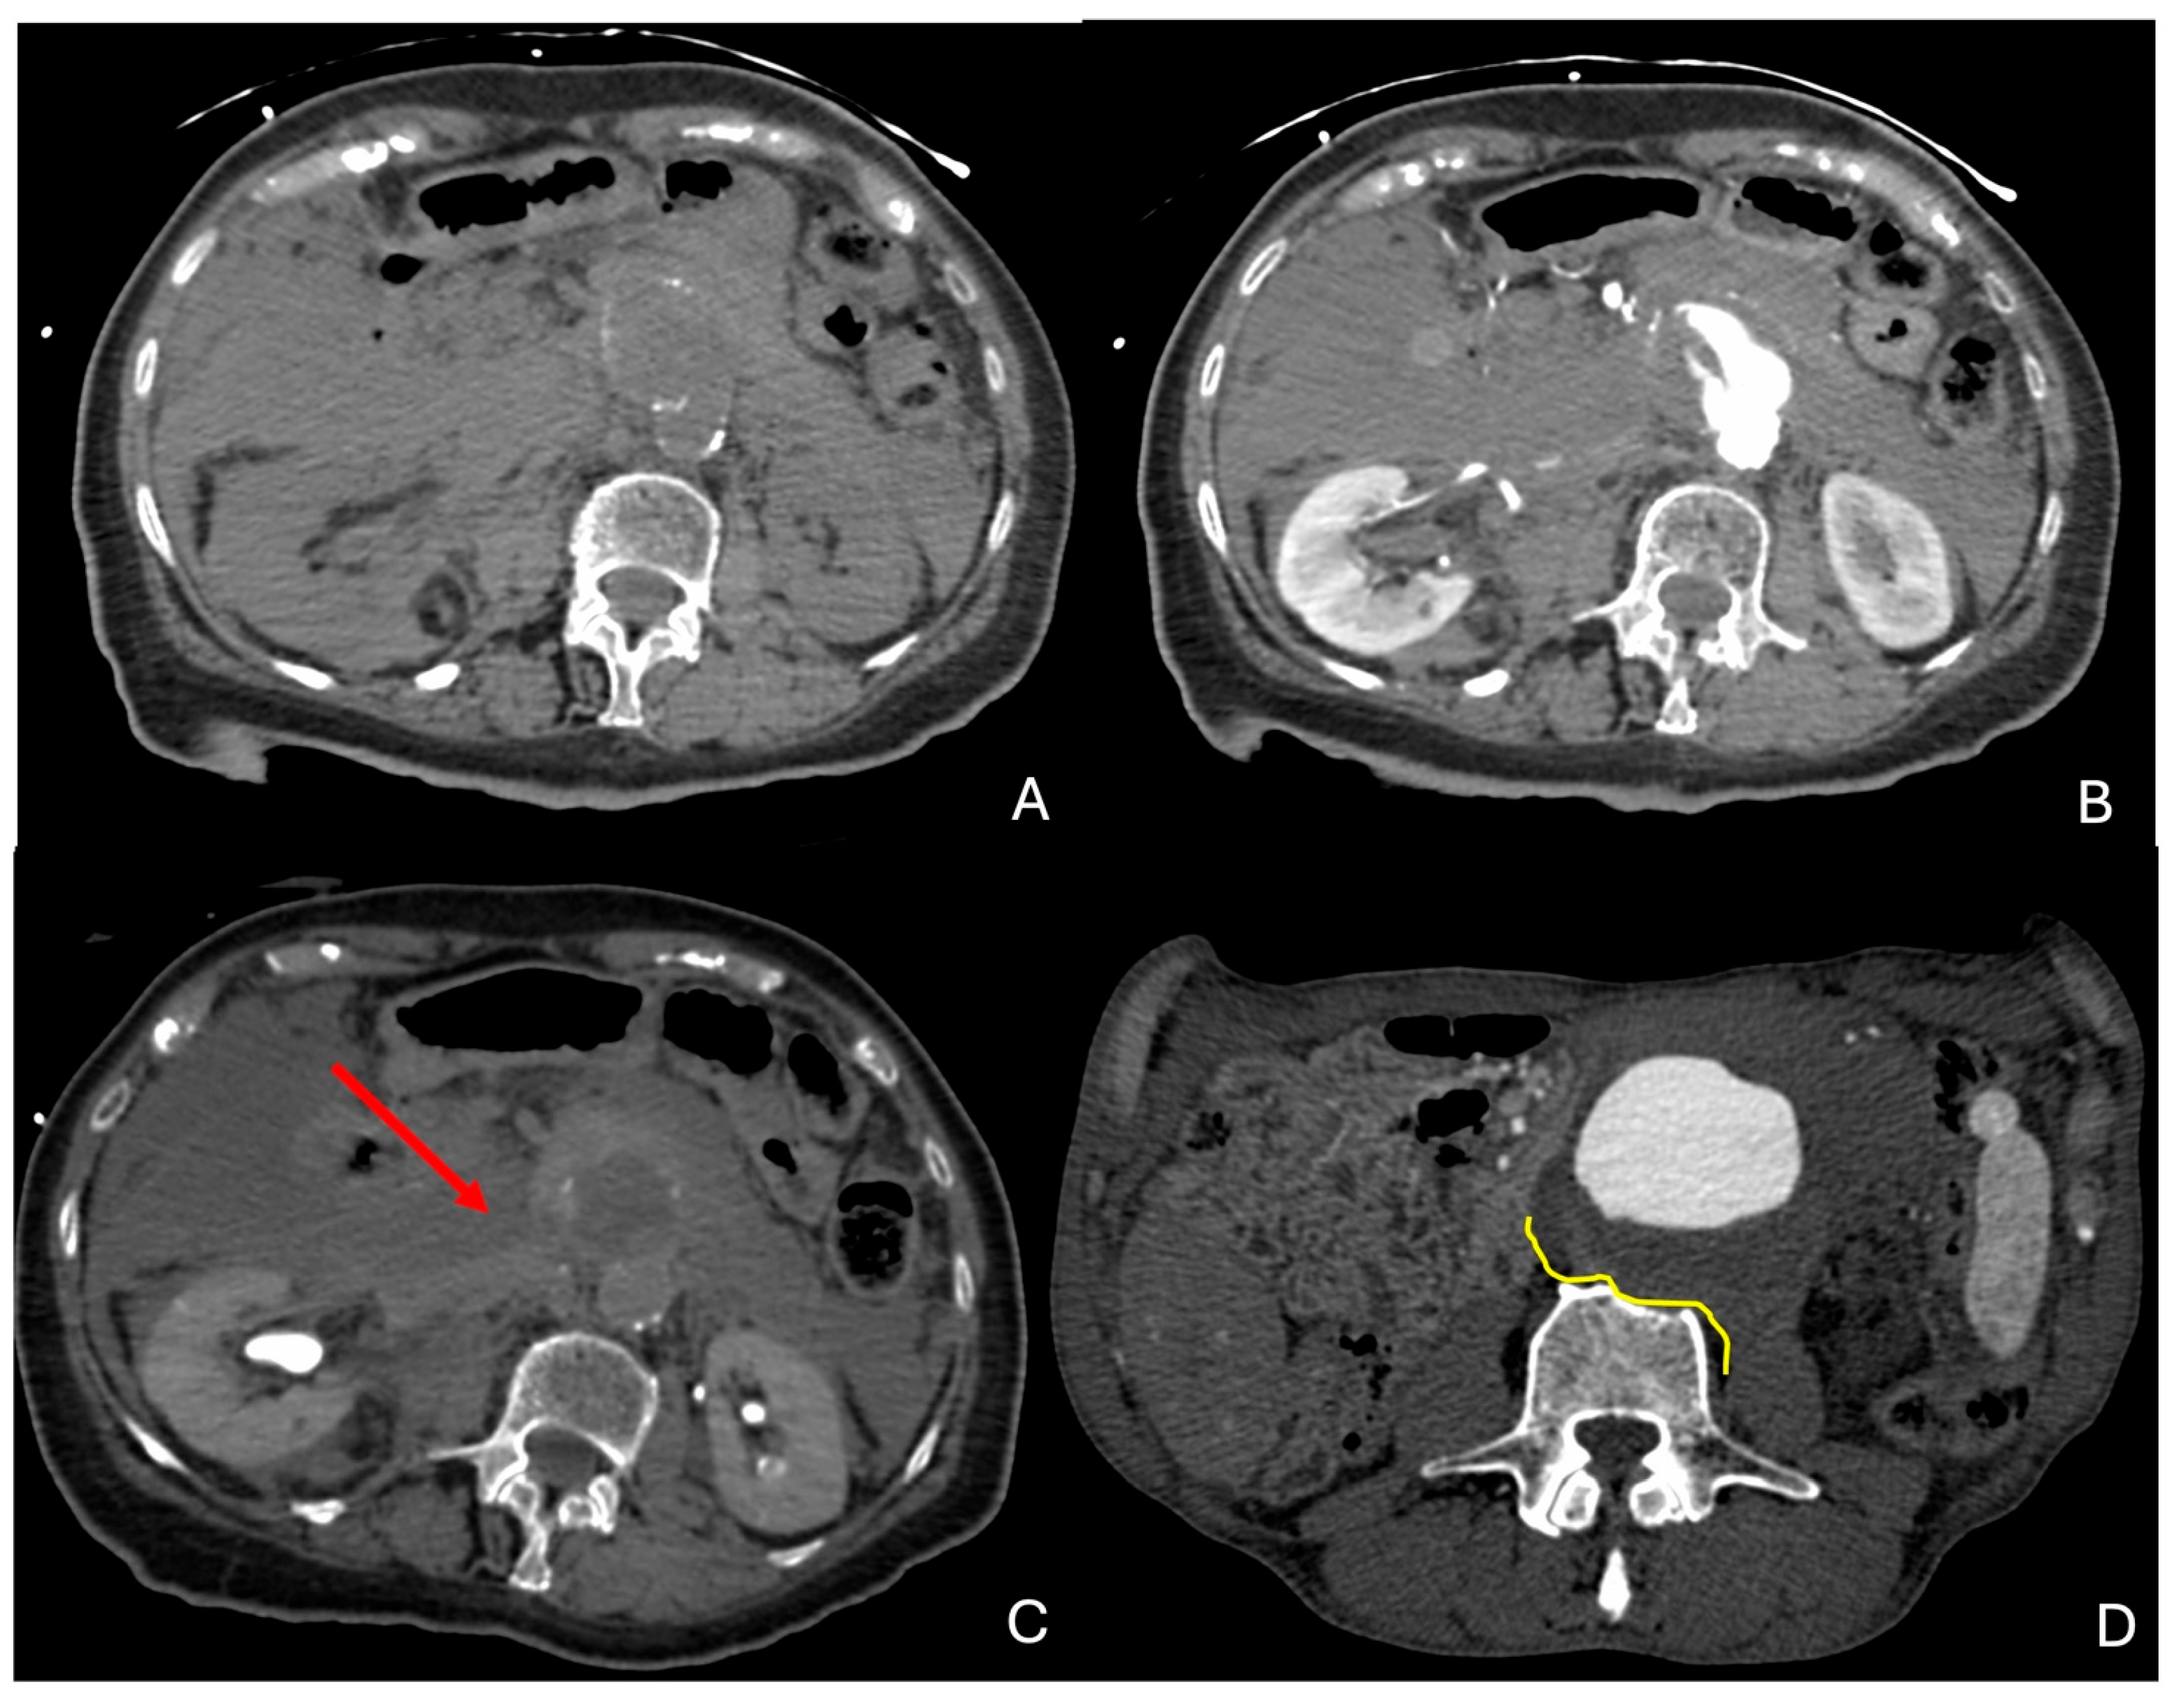

- Rakita, D.; Newatia, A.; Hines, J.J.; Siegel, D.N.; Friedman, B. Spectrum of CT Findings in Rupture and Impending Rupture of Abdominal Aortic Aneurysms. RadioGraphics 2007, 27, 497–507. [Google Scholar] [CrossRef]

- Schwartz, S.A.; Taljanovic, M.S.; Smyth, S.; O’Brien, M.J.; Rogers, L.F. CT Findings of Rupture, Impending Rupture, and Contained Rupture of Abdominal Aortic Aneurysms. Am. J. Roentgenol. 2007, 188, W57–W62. [Google Scholar] [CrossRef]